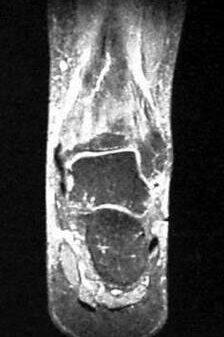

02 Überlastung des Knochens. Magnetresonanztomografie (MRT)